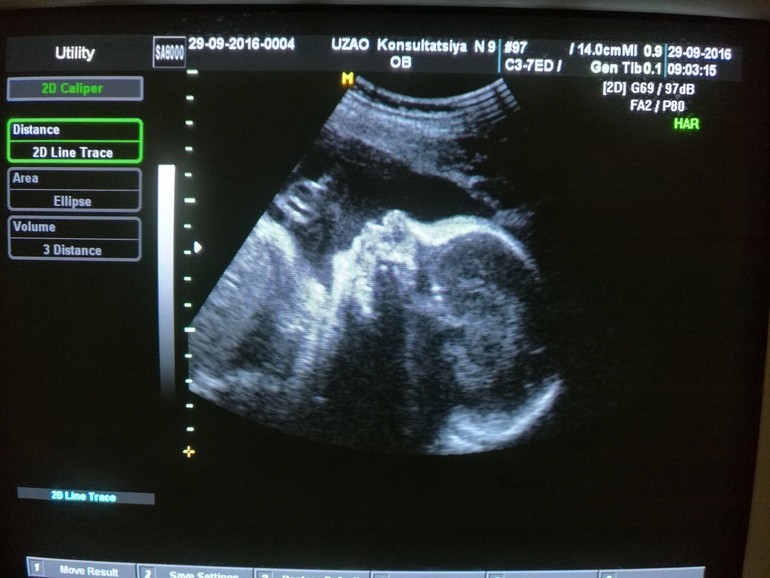

И заодно отправила меня к УЗИстке на допплер, который тоже видимо уже давно был. Допплер делала Сапрыкина Варвара Валентиновна (ЖК 9) - за ней обычно все охотятся, она и в платной клинике без работы никогда не сидит.. и тут к ней ажиотаж.. Она и правда прекрасна. Впервые мне сделали стоп-кадр личика, хотя я даже не просила:) И уже и не надеялась. Так что вот она, моя красотка:

Подтвердили девочку, хотя вначале ей что-то там показалось другое.. но переложив меня на бок, покрутив.. все-таки сказала девочка.. :) Ну будем знать и закупать одежку:)